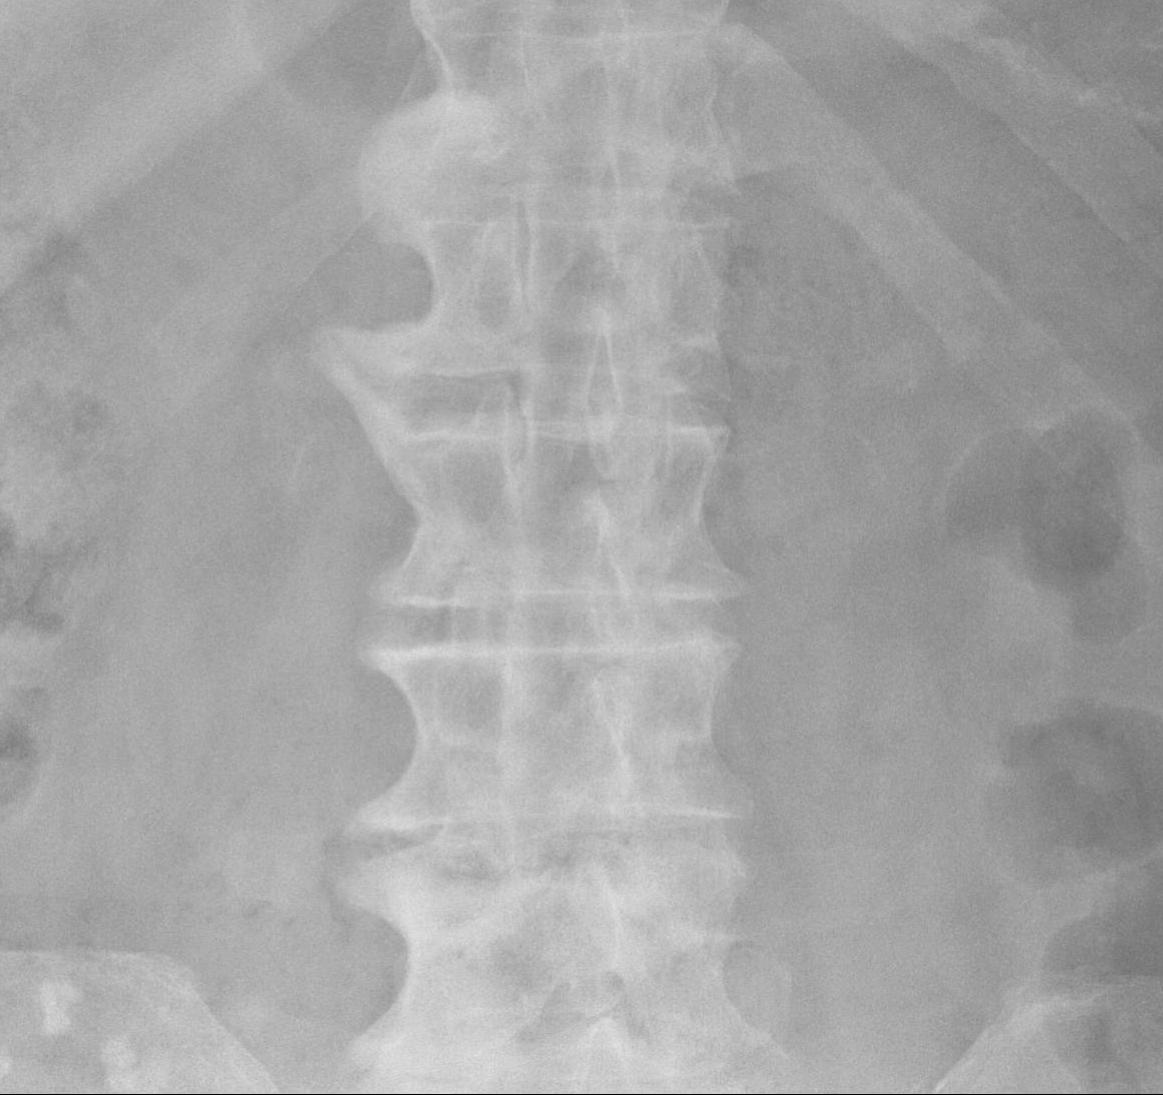

X-ray

Thoracic vertebra

Most common right sided and unilateral

- anterior & lateral spine

Non marginal syndesmophytes

- flowing / candle wax

Integrity of disc spaces & facet joints maintained

Lumbar spine

- least common